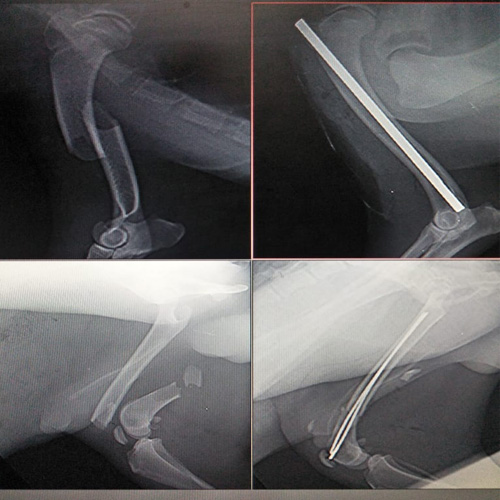

d. Orthopedic surgery

Read moreOur Gallery